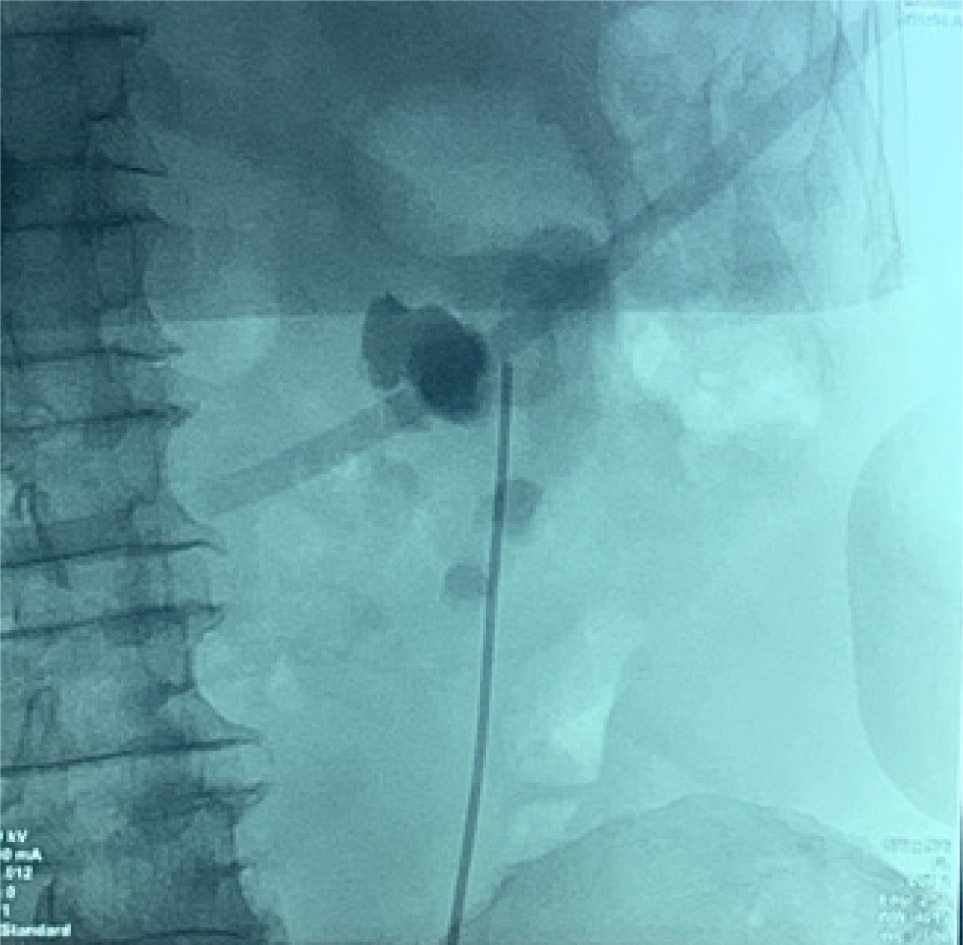

Bilateral RP and ureteric catheterization were first performed for the identification of the hila and calyces of the HSK (Figures 4 & 5). A lower midline laparotomy was performed. The tumor was identified, measuring 7 cm in diameter (Figure 6). Careful dissection of complex hilar structure was performed. Two renal arteries and two renal veins supplying the right side were identified and slung (Figure 7). The tumor was resected with artery clamping (Figure 8). The right lateral calyx of the pelvicalyceal (PC) system was involved and resected. The PC system was closed with 3/O PDS. Renorrhaphy was completed with 3/O V-Loc, and parenchyma was closed with 2/O V-Loc. Ischemic time was 20 minutes, and total operation time was 332 minutes. Blood loss was 420 mL. The patient had completed 1 week of levofloxacin and was discharged on postoperative day 6 with one kick of fever that spontaneously subsided.

Figure 4: Left renal pelvis.

Figure 5: Right renal pelvis.

Moreover, challenges may arise when conventional imaging methods such as CT scans and 3D reconstructions fail to provide a clear depiction of the renal pelvis, leading to uncertainties regarding its boundaries and internal structure. In such instances, intraoperative strategies become crucial, including RP of the renal pelvis and collecting system to guide surgical decision-making. In addition, the intraoperative injection of the dye can be utilized to confirm the precise location of the renal pelvis, aiding in surgical navigation. Real-time imaging techniques using fluoroscopy at key junctures in the procedure, such as before making incisions, prior to tumor removal, and after closing the renal pelvis, offer valuable insights and guidance in managing the unclear structures effectively. Employing on-table surgical planning based on real-time imaging data becomes essential in adapting to unforeseen challenges and ensuring optimal treatment outcomes for RCC within the unique anatomical context of an HSK.

We have effectively utilized intraoperative RP to enhance surgical precision in mapping the intricate anatomy of the renal pelvis. Unlike previous methods relying on CT scans and 3D reconstructions, which often fall short in detailing the exact drainage pathways from the renal pelvis to the ureters in cases of HSKs, intraoperative RP provides invaluable insights. This technique enables our surgical team to gain a comprehensive understanding of the renal drainage system, crucial for ensuring that the renal pelvis remains open and connected to the appropriate structures following partial nephrectomy. In essence, intraoperative RP serves as a vital and secure tool for urologists, empowering them to navigate the complexities surrounding anomalous renal pelvis structures with precision, thereby mitigating the risks of postoperative complications.